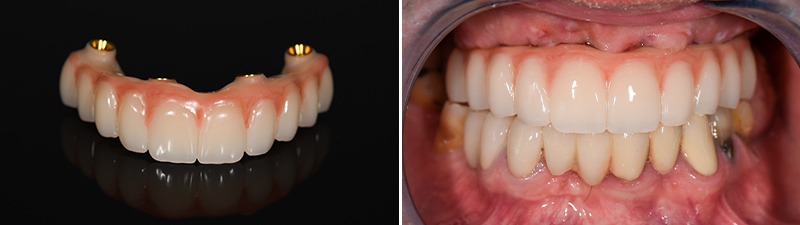

Fig. 08 : bridge provisoire PMMA avec gencive composite sur TiBase IPD et bridge provisoire en place post chirurgie.

Fig. 09 : photo à 6 mois post-opératoire.